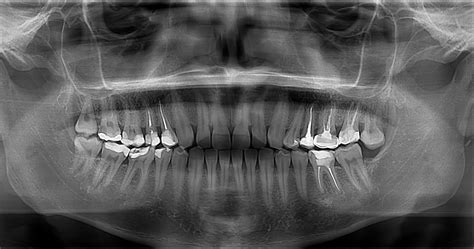

Las radiografías panorámicas son especialmente útiles para diagnosticar dientes incluidos o retenidos, es decir, aquellos que no han erupcionado completamente o que están atrapados en el hueso. Antes de iniciar un tratamiento ortodóncico, es fundamental tener una imagen completa de la disposición dental y ósea.

Además, se puede planificar el tratamiento de ortodoncia, detectar la presencia o evaluar el desarrollo de las muelas del juicio y examinar la salud de los huesos y tejidos que sostienen los dientes.

- La radiografía panorámica es clave para identificar problemas dentales que no son visibles a simple vista.

- Las caries que se forman entre los dientes o debajo de empastes antiguos pueden pasar desapercibidas durante un examen visual.

- La pérdida de hueso alrededor de los dientes, uno de los principales indicadores de la periodontitis, es fácilmente visible en una radiografía panorámica.

- Esta técnica es especialmente útil para detectar quistes dentales, tumores benignos y otros problemas óseos que podrían pasar desapercibidos.

- Otro de los aspectos que no se pueden advertir a simple vista en una exploración ordinaria es el de los dientes que no han erupcionado de la encía.

En conjunto, una radiografía panorámica ofrece una visión detallada que permite diagnosticar diversas condiciones dentales, desde caries hasta problemas de las encías y anomalías en la posición de los dientes.

Usos de la radiografía panorámica dental.